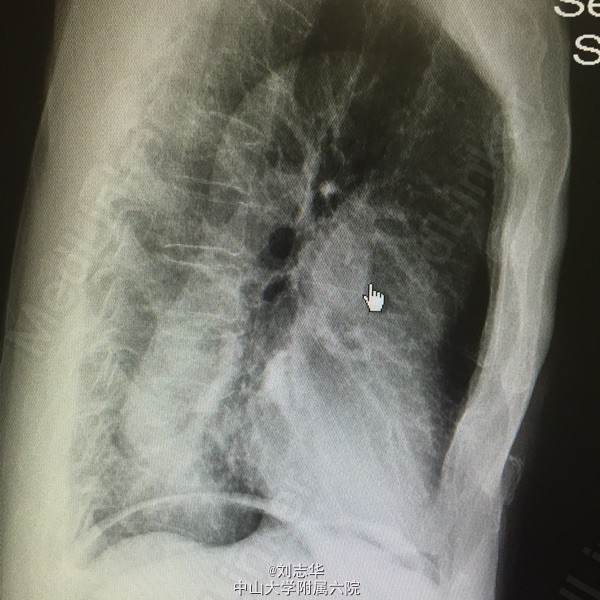

患者男,64岁,两年前于外院因"胃溃疡穿孔"行"胃大部切除术"。一天前无明显诱因出现上腹疼痛,程度剧烈,刀割样,急诊行腹平片检查:双膈下游离气体。

查体:上腹部10cm手术疤痕,全腹压痛反跳痛明显。肠鸣音1-2次/分。余无特殊。 腹平片:双膈下游离气体。